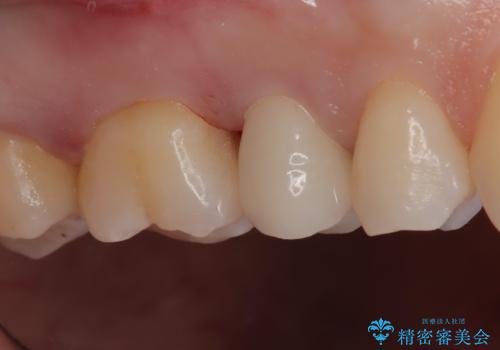

【セラミックインレー】定期検診にて虫歯を発見

- 定期検診にて虫歯を発見したため、セラミッククラウン、セラミックインレーにて治療を行いました。

小臼歯の虫歯は歯髄に近かったため、部分的断髄法にて歯髄を部分的に保存した治療をおこなっています。